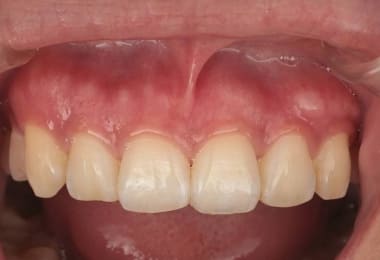

Before

1週間後

After

2週間後